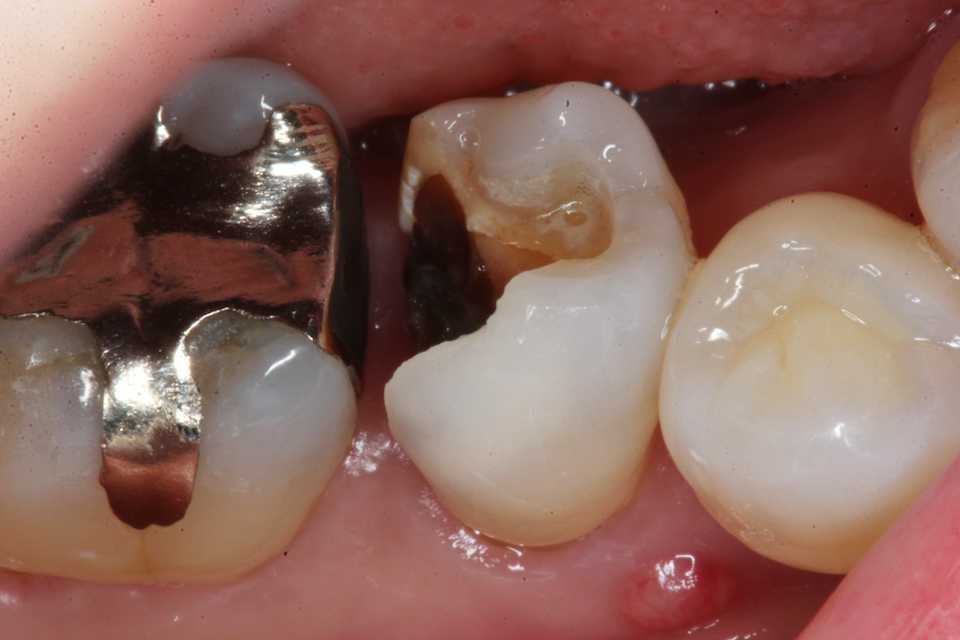

30代女性、右下7、Per、歯牙破折、歯根吸収?ほとんど抜けそうな(抜けている)状態で来られた。ご本人にお訊きしてもどうしてこうなったのか記憶にないそうだ。とりあえずレントゲン写真でのbefore/afterだが、近心の歯根が半分無くなっている。吸収されたのか、破折して破折片がどこかに行ってしまったのか、よく分からない。とりあえず抜いてみるしかない。beforeafter処置前はセラミック系の冠が装着されていたが、グラグラしている。冠は横から切断して除去した。歯根は前後(近遠心的)に破断していてグラグラしているのを確認した。どこまで健全歯質が残っているか軟化象牙質を削除しながら見てみたが、切削バーが届く範囲で健全歯質を確保するのはできなかった。抜歯してみないと正確なところは分からない。抜歯して直視下で見ないと軟化象牙質を除去し、健全歯質を出すことはできない。健全歯質の新鮮面を出さないとスーパーボンドは接着しないので、歯根の再建はできないということになる。抜歯再植は次回にすることにしてα-TCPで仮封鎖した。つづく